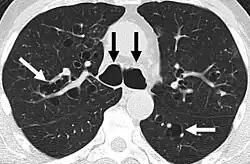

A chest X-ray is abnormal in most patients with bronchiectasis. Computed tomography is recommended to confirm the diagnosis and is also used to describe the distribution and grade the severity of the disease. Radiographic findings include airway dilation, bronchial wall thickening, and atelectasis.[65] Three types of bronchiectasis can be seen on CT scan, namely cylindrical, varicose, and cystic bronchiectasis.[66]

Bronchiectasis primarily in the middle lobe of the right lung -

Bronchiectasis secondary to a large carcinoid tumor (not shown) that was completely obstructing the bronchus proximally. Dilation of the airways is present.